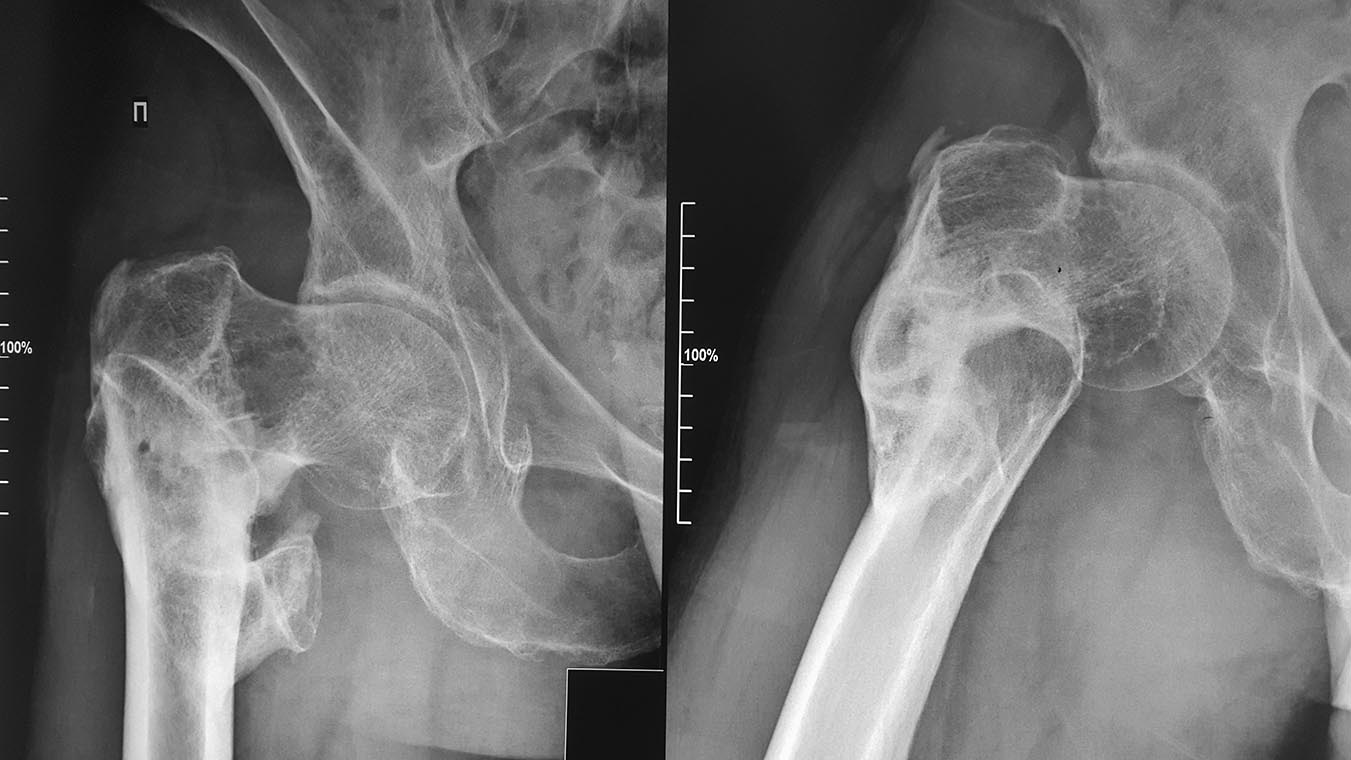

Уважаемые коллеги,нужен ваш совет по тактики лечения посттравматической деформации проксимального отдела бедра. Пациент 47 лет.Травма в 2014 году.Лечили скелетным вытяжением. Клинически имеется укорочение - 8 см,патологическая установка н/конечности в положении наружной ротации.После обсуждения в отделении остановились на двухэтапном лечении: 1) остеотомия,АВФ таз-бедро в режиме дистракции до восстановления длины. 2) остеосинтез стержнем PFN.Интересно мнение форума по тактике, выборе импланта, режиме дистракции. С уважением, Dr.Khalimov

Надо сделать сравнительные снимки бедер. И сделать скиаграммы или в фотошопе можно - надо спланировать корекцию.

Если одна угловая коррекц ия решает проблему с длиной - то можео сделать только вальгизирующую межвертельнюую остеотомию. Если одна коррекция варуса не даст нужной длины сегмента - то для начада посмотреть, сколько не хватит длины.

Укорочение в данном случае укорочение является не только истинным, а также типа кажущимся, связанным с тем, что пациент не может полностью отвести бедро.

В таком случае восстановление оси существенно "удлинит" ногу. Останется 3-4 см, которое, собственно и будет истинным укорочением. На эту величину и нужно удлинять за счет дистракции.